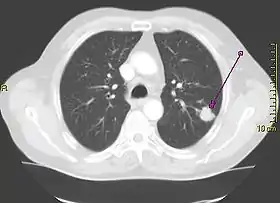

![]() | |

| A chest X-ray showing a tumor in the lung (marked by arrow) | |

A person suspected of having lung cancer will have imaging tests done to evaluate the presence, extent, and location of tumors. First, many primary care providers perform a chest X-ray to look for a mass inside the lung.[8] The X-ray may reveal an obvious mass, the widening of the mediastinum (suggestive of spread to lymph nodes there), atelectasis (lung collapse), consolidation (pneumonia), or pleural effusion;[9] however, some lung tumors are not visible by X-ray.[5] Next, many undergo computed tomography (CT) scanning, which can reveal the sizes and locations of tumors.[8][10]